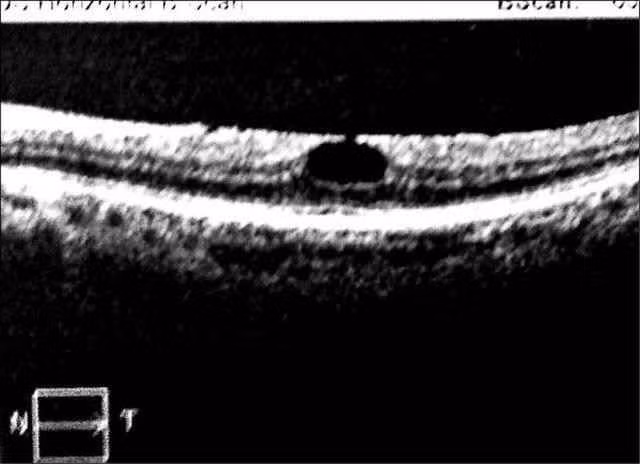

Bác sĩ Hồng Khải Đình, Trưởng Khoa Mắt của bệnh viện, sau khi khám phát hiện 2 mắt của Tiểu Hoàng đều bị cận thị, sau khi tiến hành điều trị tật khúc xạ, mắt trái giảm còn dưới 0.5 độ, nhưng mắt phải vẫn cận 1.0 độ. Bác sĩ Hồng Khải Đinh lại tiếp tục tiến hành chụp cắt lớp quang học (OCT) phát hiện mắt phải của Tiểu Hoàng bị phù nề lớp tế bào võng mạc và xuất hiện một lỗ to.

Lỗ thủng trên lớp tế bào võng mạc

Trải qua 3 tháng điều trị, mắt phải của Tiểu Hoàng đã hồi phục, lỗ to xuất hiện ở võng mạc đã biến mất. Bác sĩ Hồng Khải Đình nhắc nhở: Dưới ánh nắng gắt, mọi người nên mang kính chống nắng hoặc không sử dụng điện thoại quá 3 tiếng.